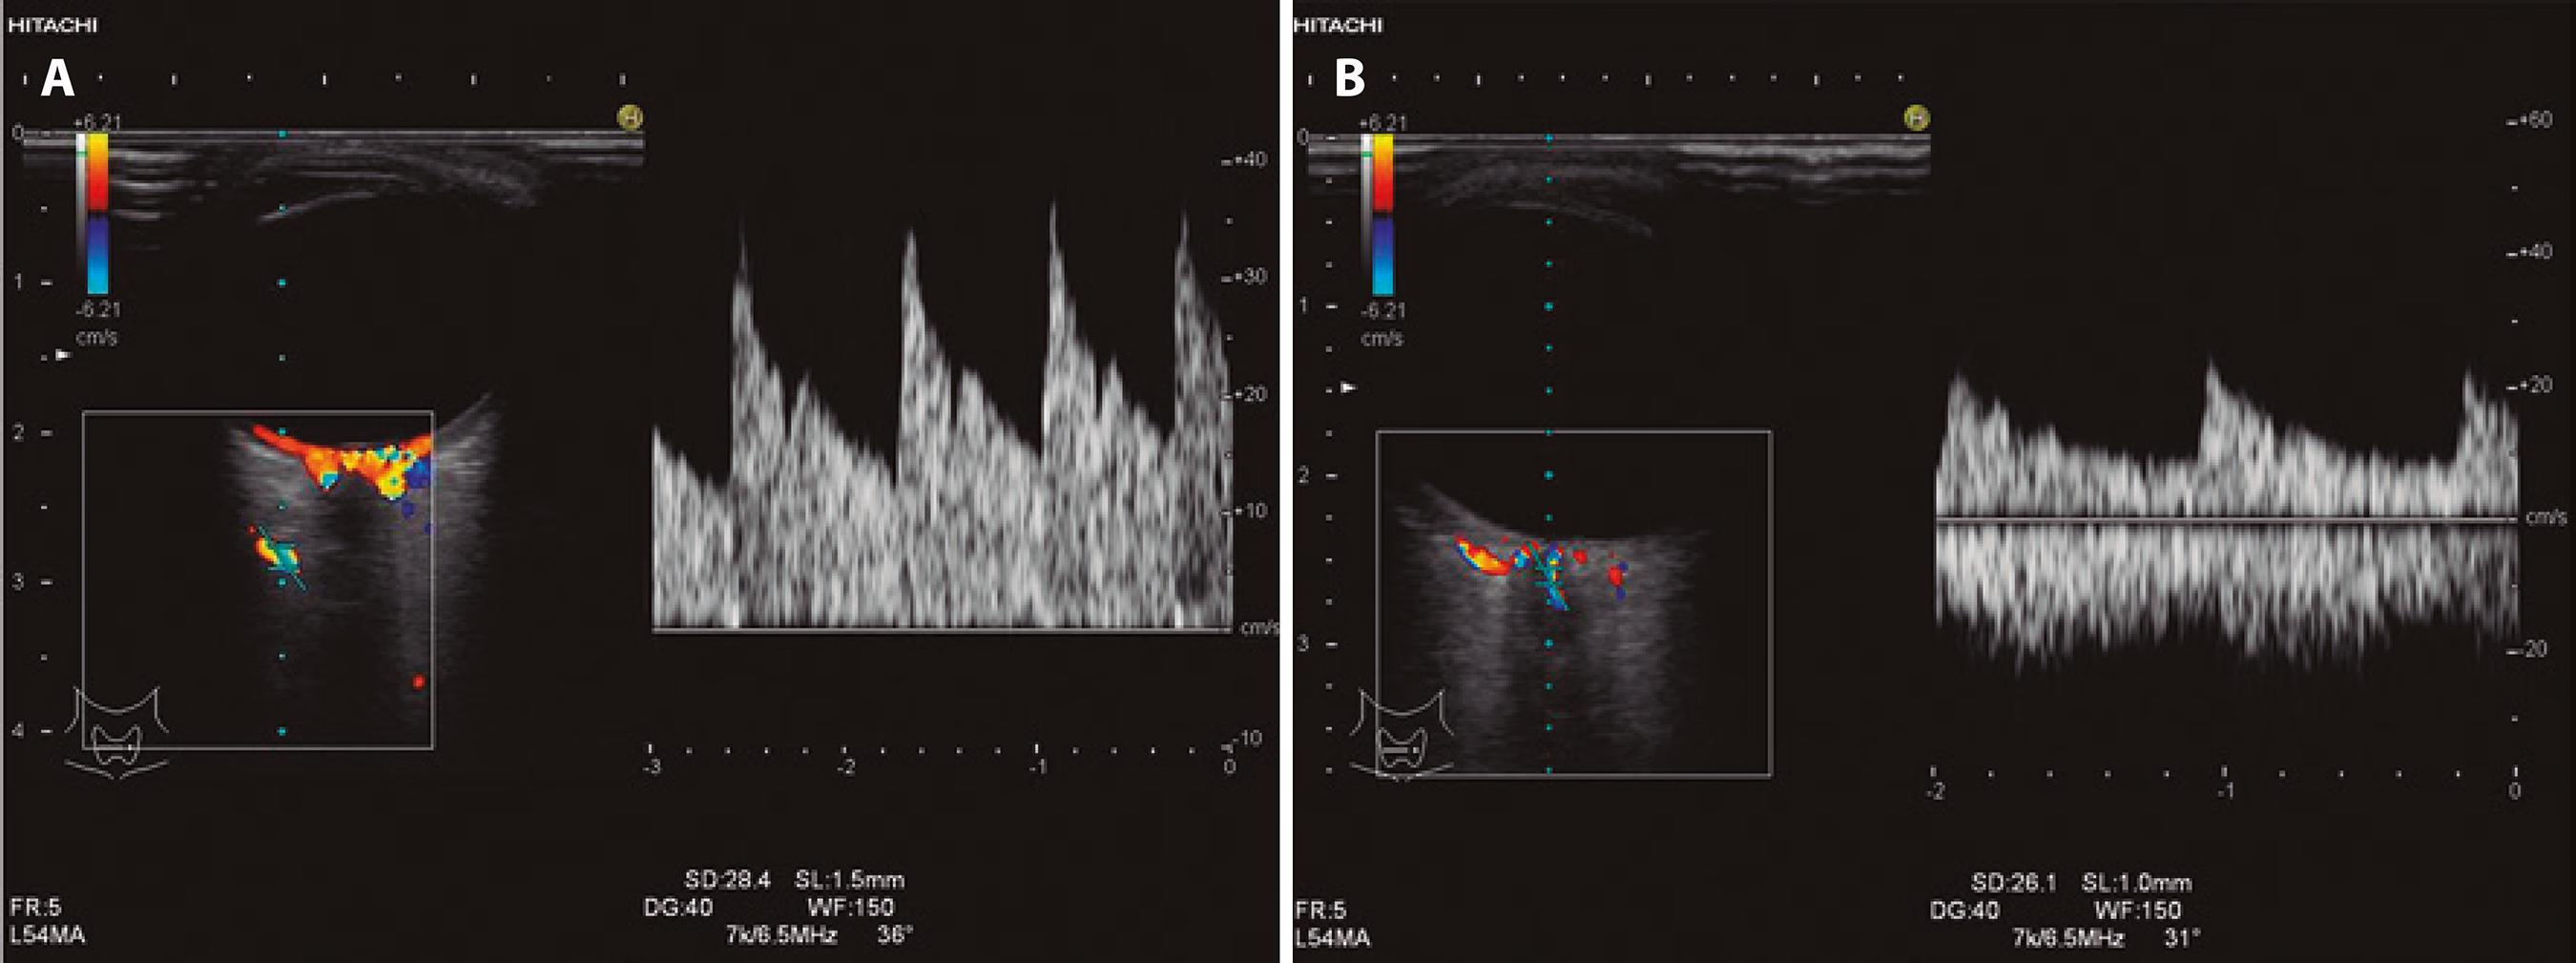

The eye was examined in transaxial, sagittal, and oblique sections. Intraocular, retrobulbar, and intraorbital anatomical structures were assessed by gray-scale ultrasonography, and the retrobulbar vessels were then examined using CDU. The patient was asked to look in the contralateral direction to allow the ophthalmologist to trace the retrobulbar course of the ophthalmic artery (OA). The OA is located approximately 20 mm posterior to the globe, below or above the optic nerve, and the central retinal artery (CRA) is found approximately 10 mm from the optic nerve in the retrolaminar region. The scanning angle is easily corrected in this region because the vein follows a straight course. The angle of the cursor was kept parallel to the blood flow at all times, at between 30° and 60°. The Doppler sample volume was 1.5 mm for the OA and 1 mm for the CRA depending on the diameter of the examined artery.

We did not perform CDU evaluation of the short posterior ciliary arteries (SPCAs) in this study because of the small size and extreme tortuousness of these vessels, which result in low reliability of any angle correction. Further, SPCAs cannot be measured individually by CDU. The anatomy of these vessels is highly variable between different individuals and both anastomoses and narrowing are common(15,16); therefore, we did not include CDU evaluation of SPCAs. We standardized the Doppler parameters for all individuals as follows: Doppler wall filter=150 Hz; Doppler gain=400; pulse repetition frequency=7k/6.5 MHz.

Peak systolic velocity (PSV), end-diastolic velocity (EDV), pulsatility index (PI=[PSV-EDV]/mean velocity), and resistive index (RI=[PSV-EDV]/PSV) were measured in all studied arteries. Time-ve locity waveforms of the OA and CRA are shown in figure 1 A and 1 B, respectively.